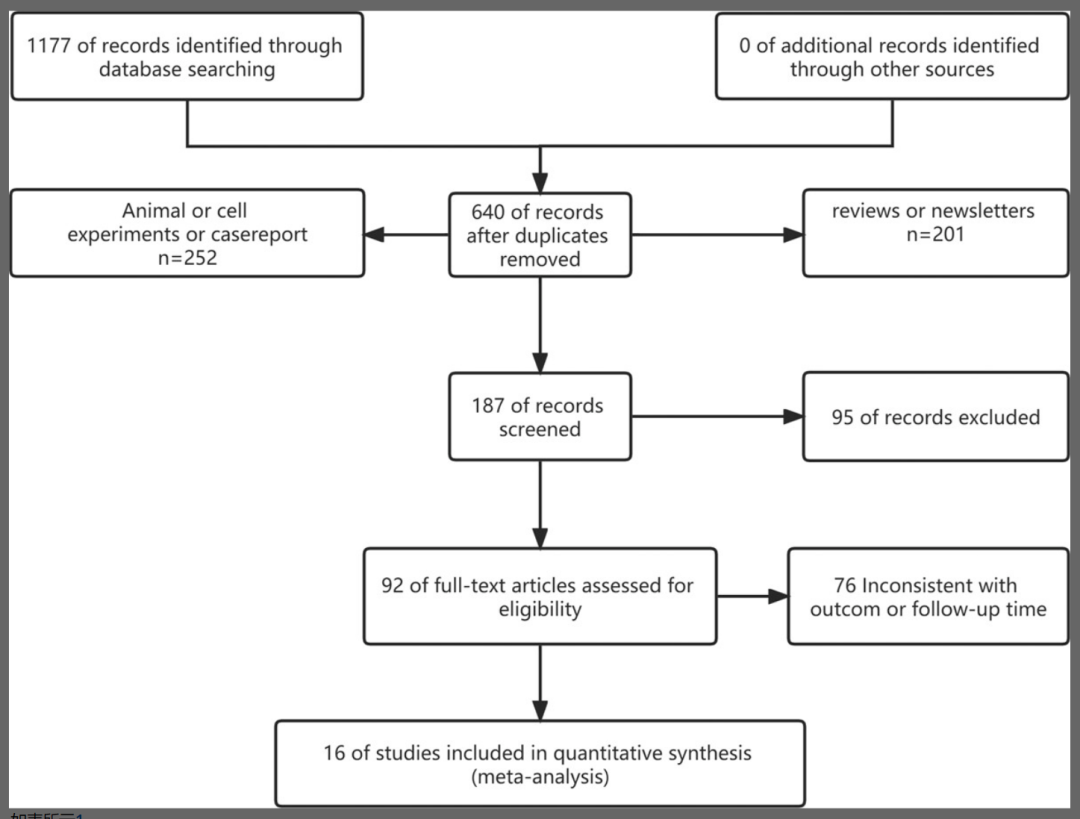

2023年11月22日,一項最新的關于膝骨關節炎干細胞注射臨床試驗的薈萃分析發表在Orthopaedic Research上。該項研究納入了16篇符合條件的臨床研究,共有875名膝骨關節炎(KOA)患者,包括干細胞移植組的441名和對照組的434名。

該項研究的作者對干細胞臨床治療膝骨關節炎的隨機對照試驗進行了薈萃分析。衡量療效的指標包括視覺模擬量表(VAS)、勒克斯指數、萊斯霍爾姆膝關節評分量表(LKSS)和西安大略和麥克馬斯特大學骨關節炎指數(WOMAC)。

在所有試驗中,9項研究評估了骨髓間充質干細胞(BMSC)移植對KOA患者的療效,2項研究評估了臍帶間充質干細胞(UcMSC)移植對KOA患者的療效,5項研究評估了脂肪干細胞(ADSC)移植對KOA患者的療效。除5項研究未說明注射干細胞的數量外,其余5項研究注射干細胞的數量在5×10^6至400×10^6之間,干細胞的平均注射量在10^6或以上。注射途徑為關節內注射。

分析結果認為,從3個月開始,干細胞移植顯著降低了VAS評分,同時WOMAC和Lequesne評分顯著降低,LKSS評分增加。這些結果表明間充質干細胞療法在臨床治療膝骨關節炎方面具有巨大的潛力。

亞組分析表明,臍帶來源干細胞和脂肪干細胞在術后的疼痛緩解效果最明顯。從緩解膝關節疼痛、促進膝關節功能恢復、減少患者創傷等角度,臍帶間充質干細胞應作為優先選擇,其次是脂肪間充質干細胞,最后是骨髓源性干細胞。

同時相關研究表明,植入關節的臍帶間充質干細胞可以形成透明軟骨,并在軟骨下形成骨組織。臍帶間充質干細胞移植治療膝骨關節炎比透明質酸鈉更快速、更顯著、更持久地減輕關節疼痛,改善關節功能,且四次注射的療效優于兩次注射。